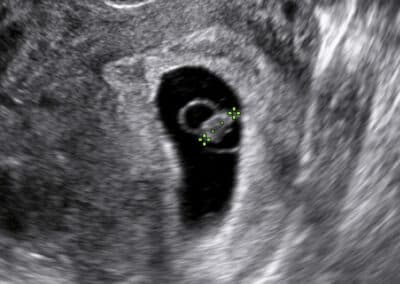

Vyšetření budoucího miminka v 8.týdnu těhotenství

Ultrazvukové vyšetření v časném (6. – 10. týdnu) těhotenství Hlavním cílem ultrazvukového vyšetření v časném těhotenství, respektive v 6.-10. týdnu těhotenství, je potvrdit normálně se vyvíjejícího těhotenství v děloze a určit jeho četnost. Do 8. týdne se vyšetření obvykle provádí při prázdném močovém měchýři přes pochvu (vaginální ultrazvuk) a od 9. týdne těhotenství při plném močovém měchýři přes břišní stěnu.

V časném těhotenství vám v našem centru vyšetříme:

umístění těhotenství v děloze, případně mimo dělohu počet miminek (jednočetné těhotenství, dvojčata, trojčata či vícerčata) srdeční akci miminka stanovíme stáří miminka a termín předpokládaného porodu od 8. týdne již zkontrolujeme základy končetin a vývoj mozku miminka